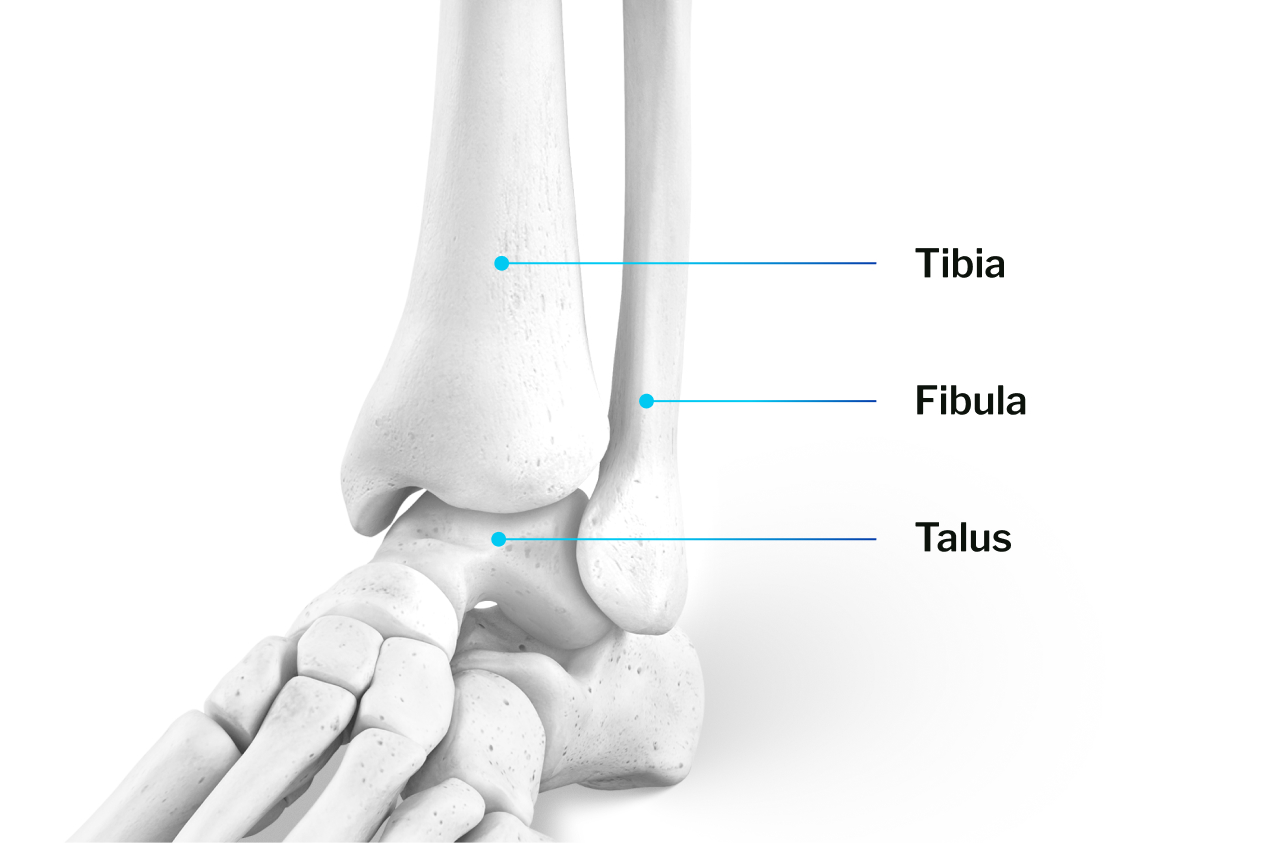

Understanding Ankle Anatomy

The ankle is a complex, free-moving joint made up of three bones:

- Tibia (shinbone)

- Fibula (outer lower leg bone)

- Talus (ankle bone that connects to the foot)

These bones form the foundation of the ankle and are covered in cartilage, a smooth layer that allows for pain-free movement.